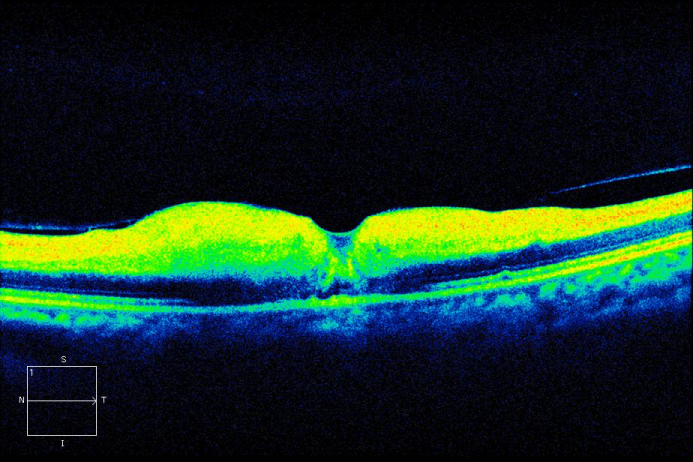

On the first postoperative day, the patient complained of poor vision in her left eye with no other associated symptoms. Brain MRI was performed to rule out intracerebral ischemia. Ophthalmology examination found no light perception, afferent pupillary defect, and a pale retina with arteriolar thinning and segmentation of macular vessels in the left eye (Figure 2 [Fig. 2]). Fluorescein angiography was performed and revealed an occlusion of the central retinal artery and the short posterior ciliary arteries. A severe interruption of blood flow was noticed on the arteriolar ramifications of the inferior retina (Figure 3 [Fig. 3]). Upon magnification, small hyperfluorescent, intraluminal spheres were noticed (Figure 4 [Fig. 4]). Optical coherence tomography (OCT) revealed hyporeflective, spherical images between 150–250 microns with posterior shadowing (Figure 5 [Fig. 5]) and thickening of the internal retinal layers due to edema and ischemia (Figure 6 [Fig. 6]). Multifocal ERG showed abnormal pattern secondary to an alteration affecting the ganglion cells of the papillomacular bundle. The patient was evaluated for a year without improvement of the visual acuity or neovascular complications in the anterior and posterior segment of the eye.

Figure 5: OCT image: Intraretinal hyporeflective spheres and their diameters.

To our knowledge this is the first report of acute central retinal arterial occlusion secondary to paraganglioma embolization and excision with Embosphere® and Contour® microparticles. Due to the late onset of symptoms we believe this was a complication of the surgical procedure per se, in which, the surgical manipulation could have eased the liberation of particles to the circulation. It remains an interrogant as to why the particles embolized directly to the central retinal artery instead of other high-flow intracerebral branches. The patient’s OCT was conclusive on the presence of hyporeflective spherical particles that confirmed the nature of the embolization. Although a rare complication, we think it must be assessed with the patient as one of the possible complications prior to embolization and surgical resection procedures.